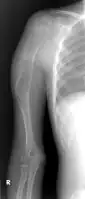

| X-ray knee - chondromyxoid fibroma in long bone of thigh near the knee | |

Chondromyxoid fibroma is a non-cancerous cartilaginous tumor, a type of bone tumor.[2][4] It usually presents with pain and swelling in a long bone of the leg in an adolescent.[1][3]

It usually presents with pain and swelling in the long bone of an adolescent.[1] Less likely affected ar ribs, spine, skull and facial bones, and tubular bones of the hand.[1]

It is rare, comprises <1 % of all bone tumors that arise from bone itself and <2% of cartilage tumors.[2] Around half occur around the knee and mostly in long bone of lower leg in the teens.[2]